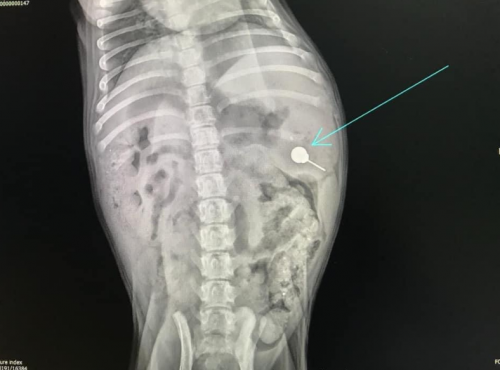

RADIOLOGIA